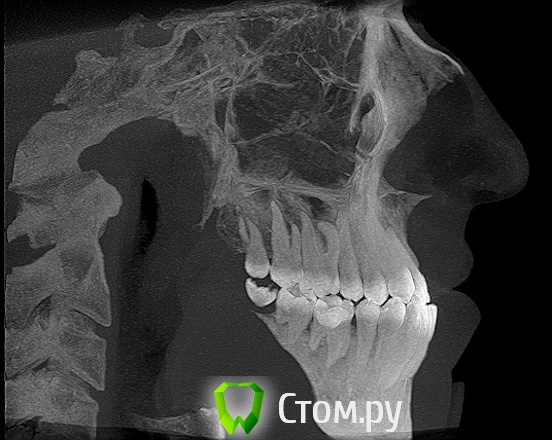

Здравствуйте! Мне 27 лет.  Очень вас прошу дать свою оценку моей ситуации. У меня сложная ситуация, я уже обошел многие ортодонтические кабинеты своего города и все говорят разное. У меня мезальный прикус, но своим профилем я доволен, я всем доволен, кроме того что у меня неправильный прикус (верхние резцы заходили за нижние и были вогнуты вовнутрь) и кривые зубки.Сейчас по рекомендации одного ортодонта ношу капу чтобы верхние резцы перепрыгнули, но теперь и это занятие меня сильно беспокоит, хотя ношу всего месяц и уже попадает зуб на зуб. Главный мой вопрос таков: "Возможно ли в моей ситуации исправить прикус без операции?" Спасибо за ответы!

можно, еще ТРГ надо,